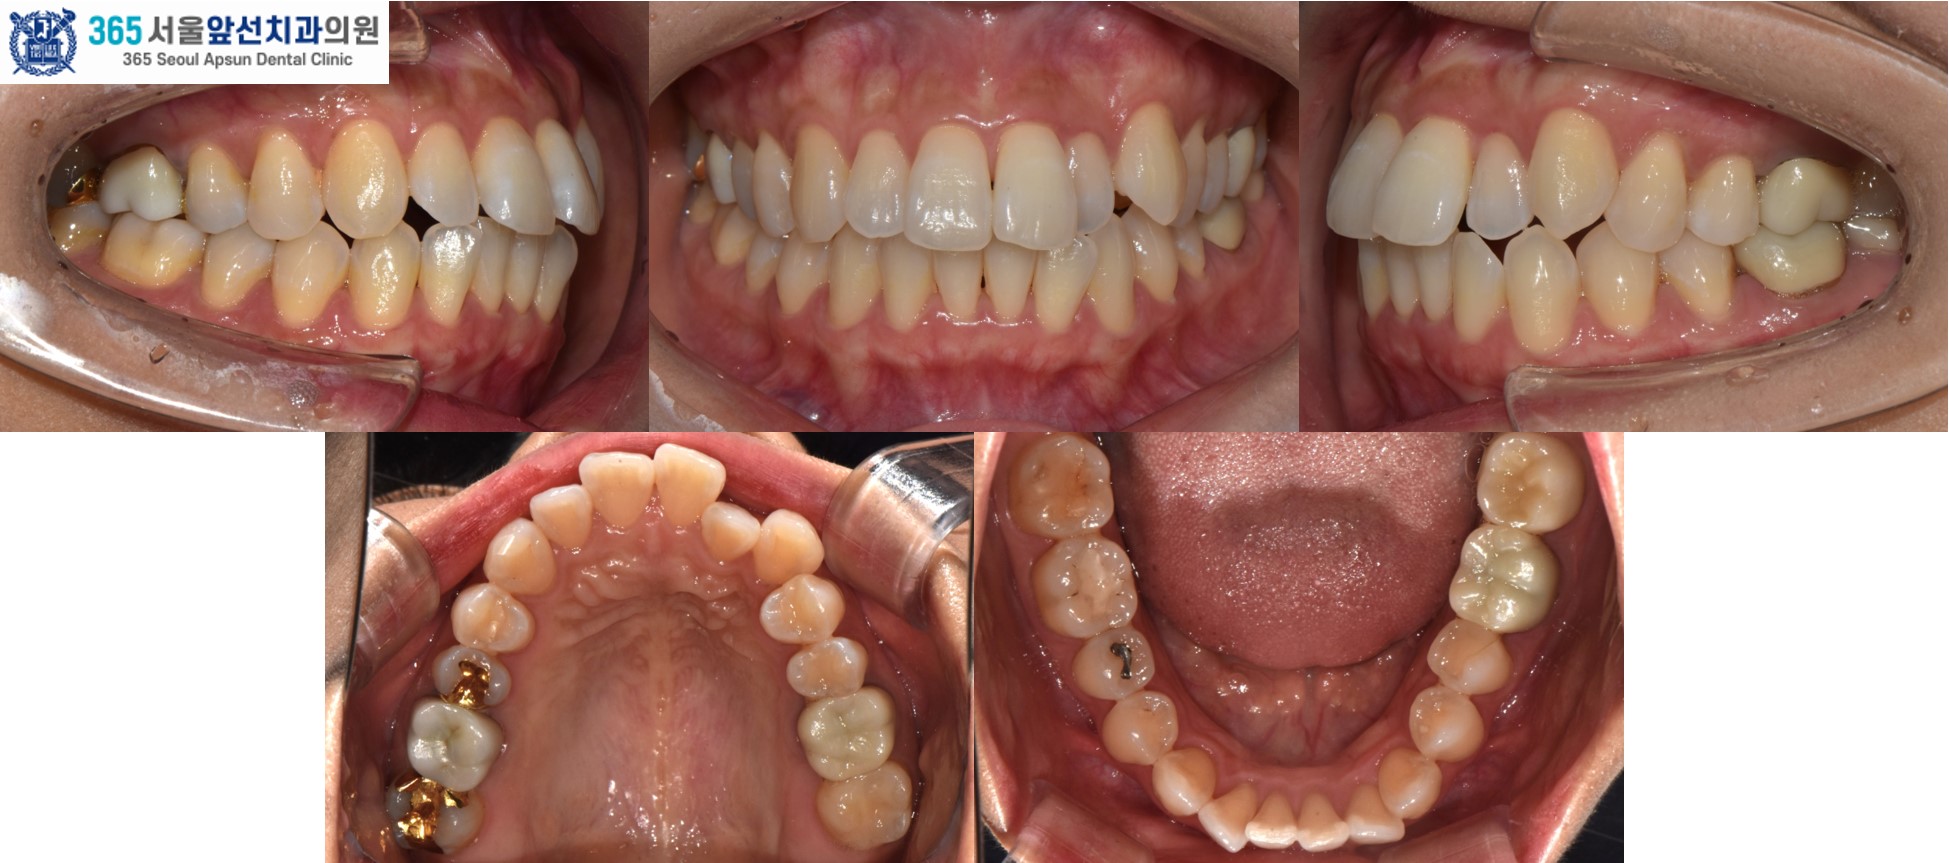

촬영일시 : 2024.11.26. / 2025.12.18. 앞니의 돌출과 반대로 물리는 앞니, 송곳니 덧니를 고민으로 내원하신 30대 여성 환자 분의 증례를 소개드리겠습니다. 치료 전, 윗니와 아랫니 사이의 거리(수평 피개)가 5.00mm, 상,하악 치열 각각 2.48mm, 2.69mm 의 필요 공간이 있는 경미한 총생(Crowding), #22 치아의 반대교합과 #23 치아의 협측 이소맹출이 관찰됩니다.

촬영일시 : 2024.11.26. 송곳니의 교합은 2급 부정교합을 보입니다. 앞니와 송곳니의 부정교합 개선을 위주로 투명 교정 치료를 계획하였습니다. 앞니의 사이즈를 감소시키면서 배열을 진행하여 수평피개를 감소하였습니다.